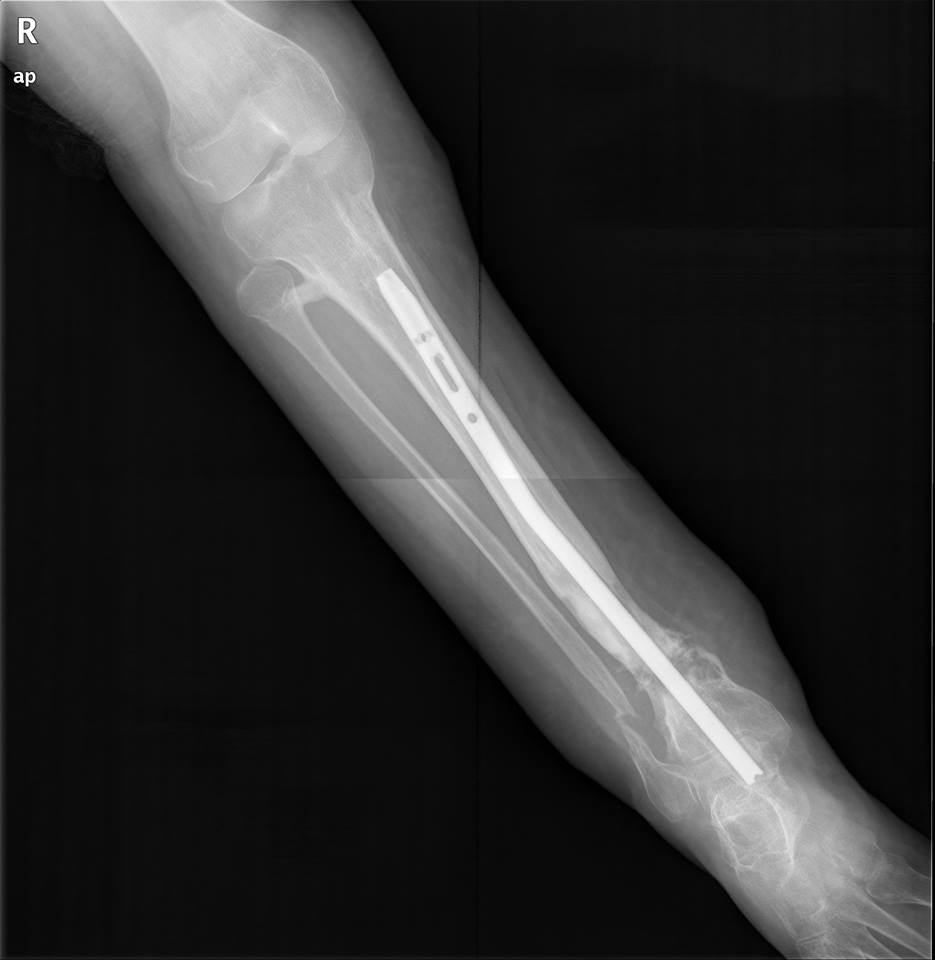

Уважаемые коллеги, Есть девушка с таким вот гвоздиком. В плане -

удаление и реостеосинтез.

Вопрос - как минимально инвазивно удалить это чудо? Понимаю, что ранее

вопрос поднимался, но тут, мне кажется, случай не стандартный. Спасибо.